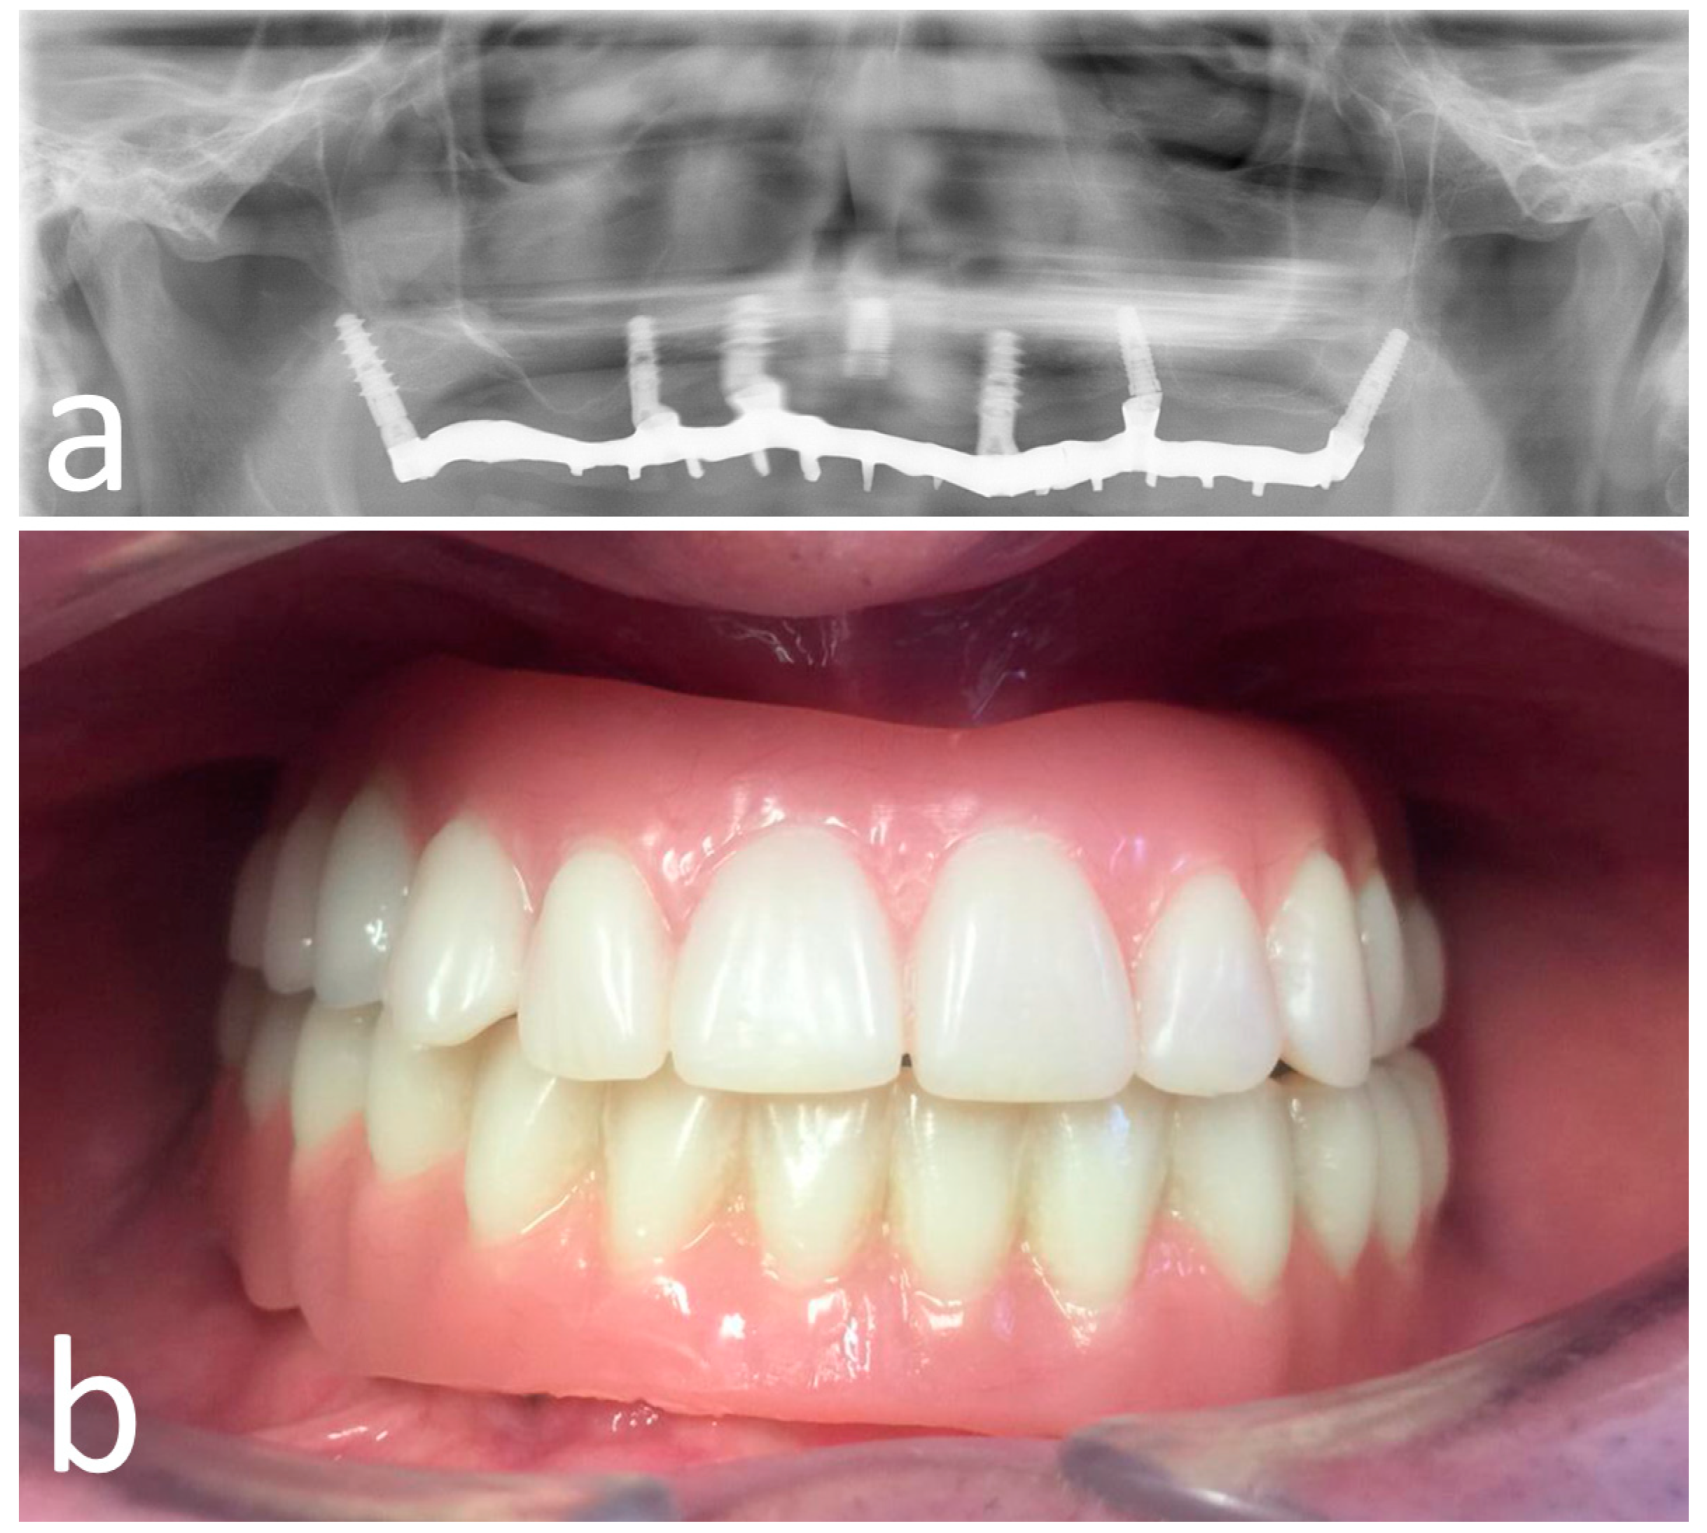

Figure 6.

OT-bridge abutments use the “Extragrade™” feature, a system allowing to compensate up to 80° of the divergence between two implants (a,b). Pictures c and d show the clinical (c) and X-ray (d) view of the provisional prosthesis using OT-bridge abutments.

Figure 7.

Opt X-ray (a) and clinical (b) view of the provisional prosthesis realized using conventional straight and angled multi-unit abutment (M.U.A.).